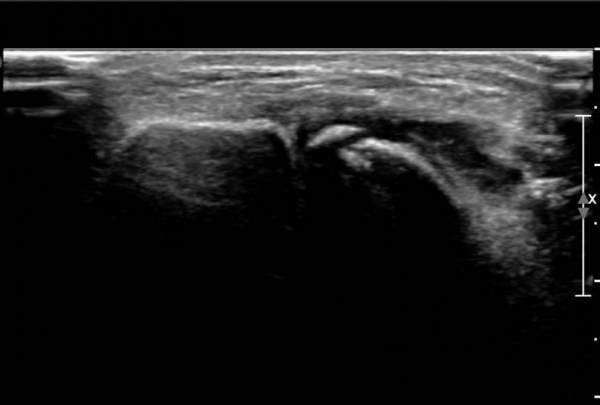

ÃÊÀ½ÆÄ ¼Ò°ß :  ¹ß¸ñ ¾Õ Á¾´Ü¸é°Ë»ç¿¡¼­ ¹ß¸ñ°üÀý³»  ¾à°£ÀÇ ¼ö¾×Àú·ù°¡ °üÂûµÊ(»çÁø 1).